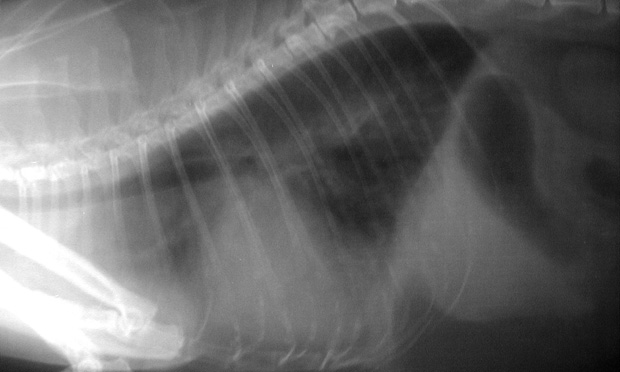

Гепарин кошке при тромбозе доза . . . . heparin . дозы гепарина являются спорным вопросом; диапазон дозировки и методов широко варьирует в рекомендациях разных ветеринарных врачей или . . .

Гепарин дозировка для кошек . Рекомендуемая дозировка гепарина для кошек - 220 м . е . кг в, спустя 3 часа - ведение поддерживающей дозы е кг четыре раза в день л к дозировку, однако, можно . Дозу следует выверять таким . .